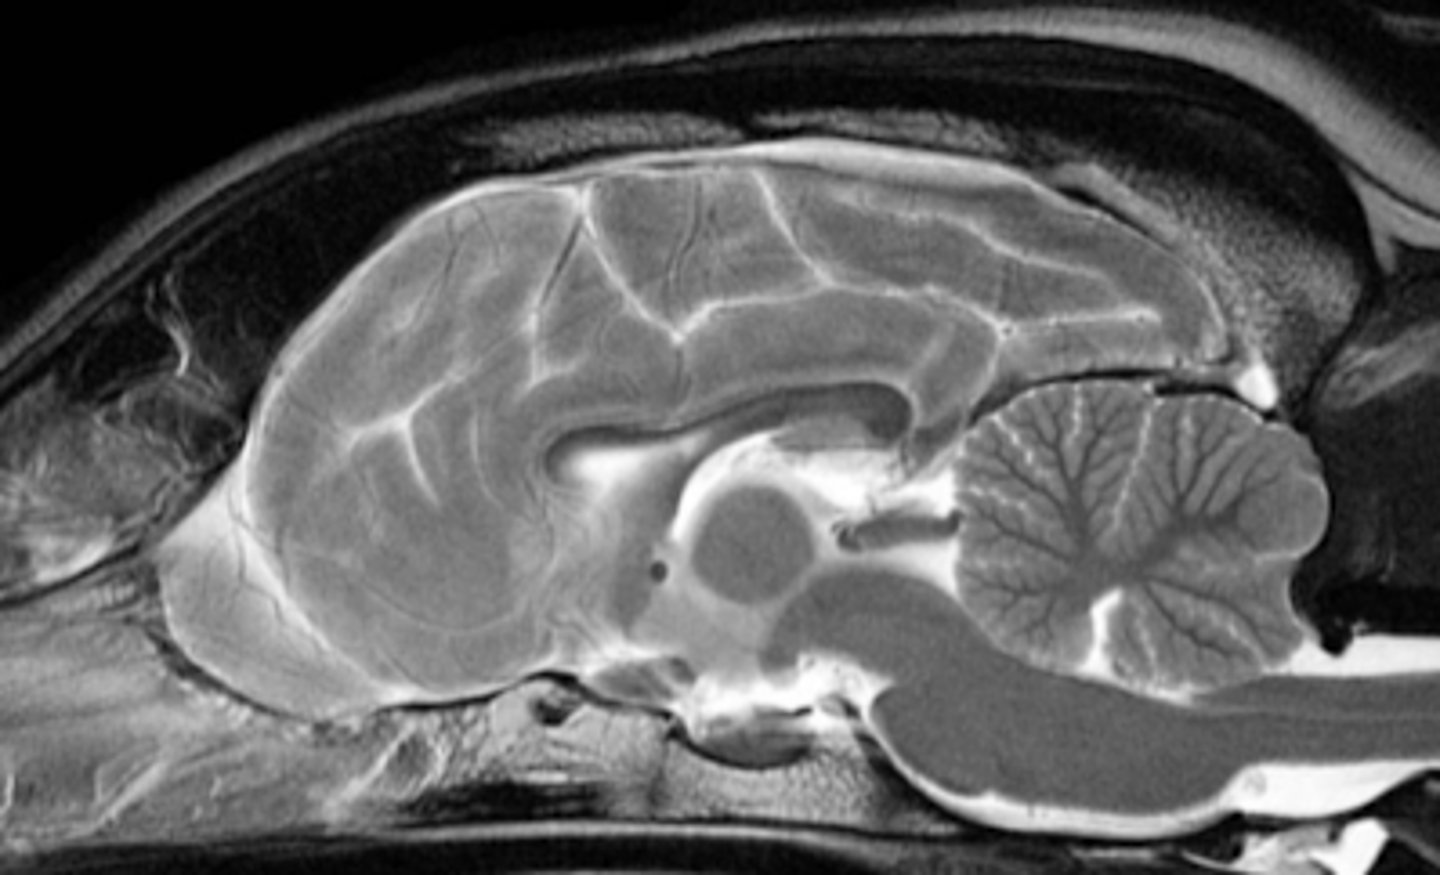

a type of imaging that uses a high power magnetic field that interacts with the body's hydrogen atoms to produce detailed images of internal body structures

what is magnetic resonance imaging (MRI)?

MRI

which type of imaging uses magnetic resonance to produce detailed images of the body's internal structures?

soft tissues, brain, spinal cord

what structures is MRI most useful for?

MRI

what type of imaging is best for visualizing the brain?

MRI

what diagnostic imaging technique was used to create this image?

MRI has NO biological effects

which is more dangerous for the body- CT or MRI?

NONE

what biological effects does MRI have?

-cannot be used in animals with any metal inside of them- even a microchip needs to be removed first

-requires 100% immobility of the patient (anesthesia)

-expensive

-takes a long time to receive the images

what are the disadvantages of using an MRI?

hyperintense

for an MRI, a structure that appears white is called...

grey

in MRI, an isointense structure appears in what color?

hypointense

in an MRI, a black structure is called....

MRI

what is this type of imaging called?